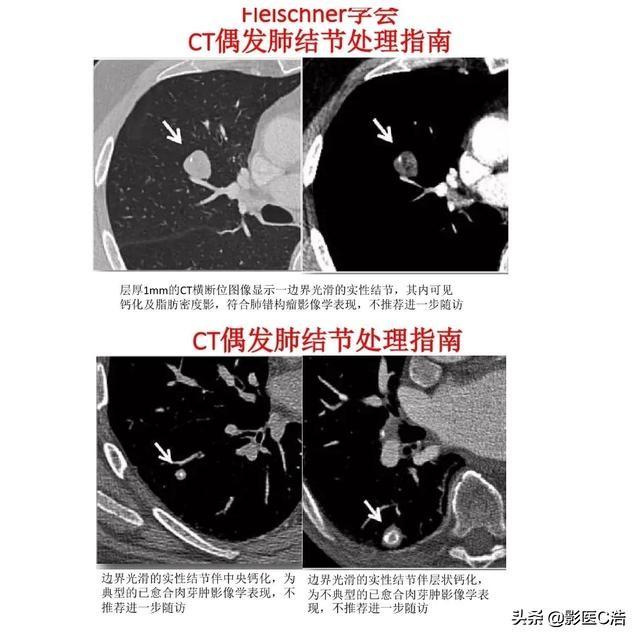

肺結節の悪性腫瘍の確率は一般に大きさに比例し、顕微鏡的結節の悪性腫瘍の確率は比較的低く、全米総合がんネットワーク(NCCN)やフライシュナー学会は、4mm~6mm未満の結節の大部分は良性、特に4mm未満は良性であるとし、経過観察を勧めていない。

良性結節は通常、丸みを帯びた形、滑らかな縁取り、炎症の場合は縁取りがぼやけるなどの規則的な形をしており、良性病変の中には、悪性である可能性がゼロではない、このような特徴的な特徴を持つものもある。例えば、典型的な肺の悪性腫瘍では、結節内に石灰化や脂肪がみられ、典型的な肺内リンパ節では、通常、胸膜下に小さな三角形の形で存在し、典型的なサルコイドーシスでは、滑らかな縁と中心部に石灰化を伴う固い結節である。